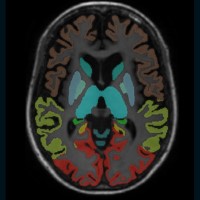

Das Modul Hirnvolumetrie ermöglicht präzise, quantitative Aussagen zu lokalen oder generalisierten Atrophien verschiedener Hirnregionen. Neurodegenerative Prozesse erkennen, bevor pathologische Werte erreicht sind.